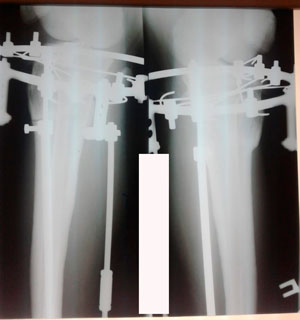

Диагноз: варусная деформация голеней.

Жалобы на боли в коленях.

Дата операции - 19.11.2019г.

на фиксации

Дата снятия аппаратов - 18.02.2020

Срок сращения - 89 дней.